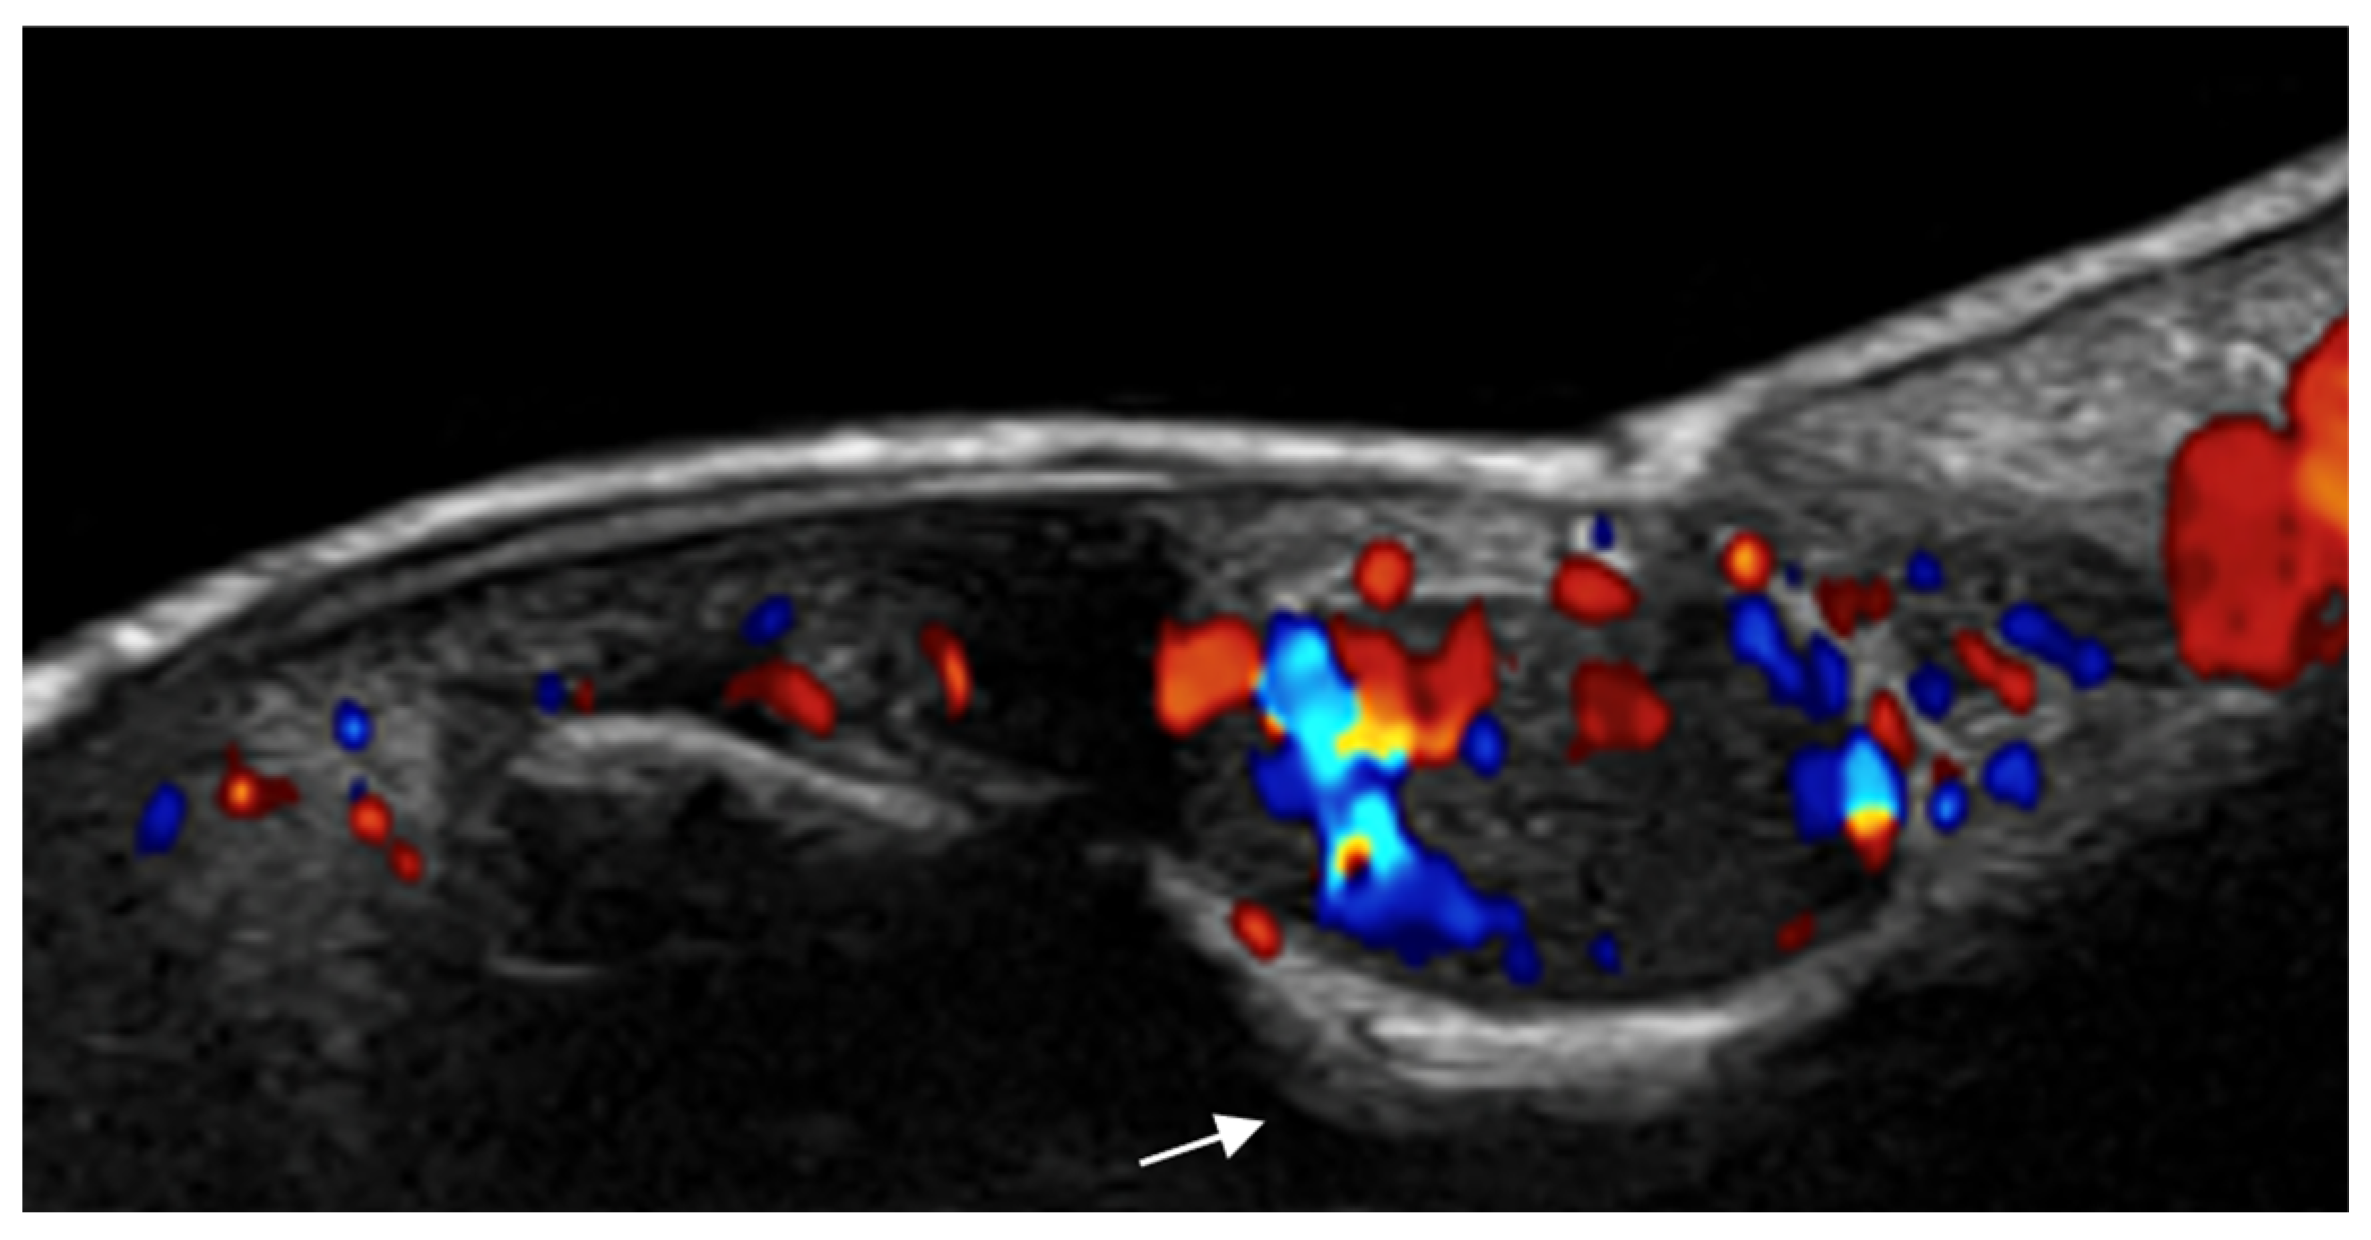

- Di Battista, M.; Vitali, S.; Barsotti, S.; Granieri, G.; Aringhieri, G.; Morganti, R.; Dini, V.; Della Rossa, A.; Romanelli, M.; Neri, E.; et al. Ultra-high frequency ultrasound for digital arteries: Improving the characterization of vasculopathy in systemic sclerosis. Semin. Arthritis Rheum. 2022, 57, 152105. [Google Scholar] [CrossRef] [PubMed]